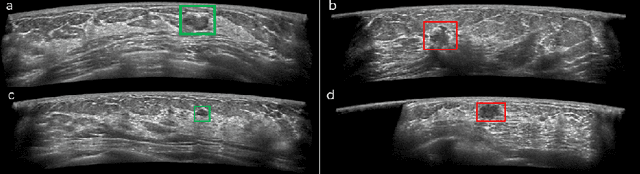

Automated breast ultrasound (ABUS) is a new and promising imaging modality for breast cancer detection and diagnosis, which could provide intuitive 3D information and coronal plane information with great diagnostic value. However, manually screening and diagnosing tumors from ABUS images is very time-consuming and overlooks of abnormalities may happen. In this study, we propose a novel two-stage 3D detection network for locating suspected lesion areas and further classifying lesions as benign or malignant tumors. Specifically, we propose a 3D detection network rather than frequently-used segmentation network to locate lesions in ABUS images, thus our network can make full use of the spatial context information in ABUS images. A novel similarity loss is designed to effectively distinguish lesions from background. Then a classification network is employed to identify the located lesions as benign or malignant. An IoU-balanced classification loss is adopted to improve the correlation between classification and localization task. The efficacy of our network is verified from a collected dataset of 418 patients with 145 benign tumors and 273 malignant tumors. Experiments show our network attains a sensitivity of 97.66% with 1.23 false positives (FPs), and has an area under the curve(AUC) value of 0.8720.